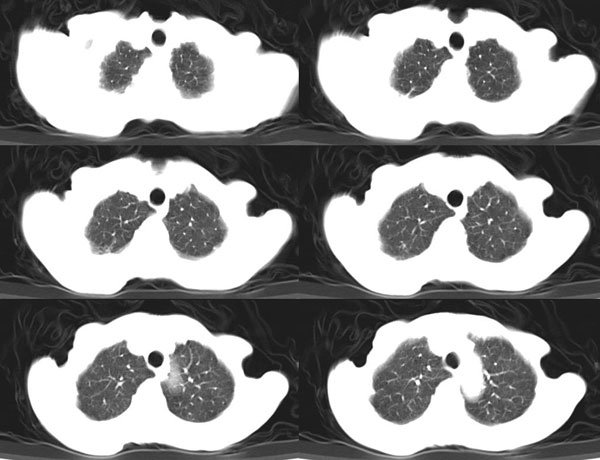

女:73岁;因一月前感冒后咳嗽,发烧,有大量脓痰,并且有恶臭味。

肺窗

右肺下叶肺脓肿

补充_____伴双肺血行播散

肺脓肿,伴有支扩

肺脓肿,伴有支扩。

考虑:1、右下肺脓肿;

2、支气管扩张合并感染。

右肺下叶示片状致密影密度不均,内见一空洞有宽液平,并可见壁结节周围示散在斑片模糊影,左下肺亦见一斑片模糊影,考虑 肺脓疡,肺癌不除外。

2,双下叶支气管扩张;

右下肺脓肿,两下叶,中叶支扩并感染,右侧胸膜肥厚粘连。

发烧,有大量脓痰,并且有恶臭味,空洞,大液平,比较典型的肺脓疡

发烧,有大量脓痰,并且有恶臭味,空洞,大液平,比较典型的肺脓疡。谢谢楼主。